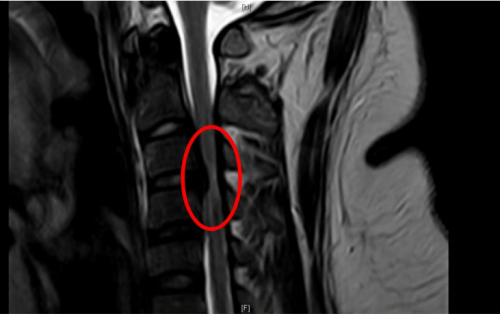

“患者体重高达320斤,属于重度肥胖,且合并高血压,经过完善核磁检查,诊断为脊髓型颈椎病、颈椎椎管狭窄、颈椎后纵韧带骨化,由于病情严重,已经造成颈椎椎管狭窄、脊髓受压变性。”香港马会app

标红部位提示颈椎椎管狭窄、脊髓受压变性